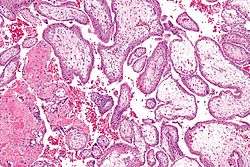

![]() Micrograph showing chorionic villi. Intermediate magnification. H&E stain. | |

Chorionic villi are villi that sprout from the chorion to provide maximum contact area with maternal blood.

They are an essential element in pregnancy from a histomorphologic perspective, and are, by definition, a product of conception. Branches of the umbilical arteries carry embryonic blood to the villi. After circulating through the capillaries of the villi, blood returns to the embryo through the umbilical vein. Thus, villi are part of the border between maternal and fetal blood during pregnancy.

Histology

The bulk of the villi consist of connective tissues that contain blood vessels. Most of the cells in the connective tissue core of the villi are fibroblasts. Macrophages known as Hofbauer cells are also present.